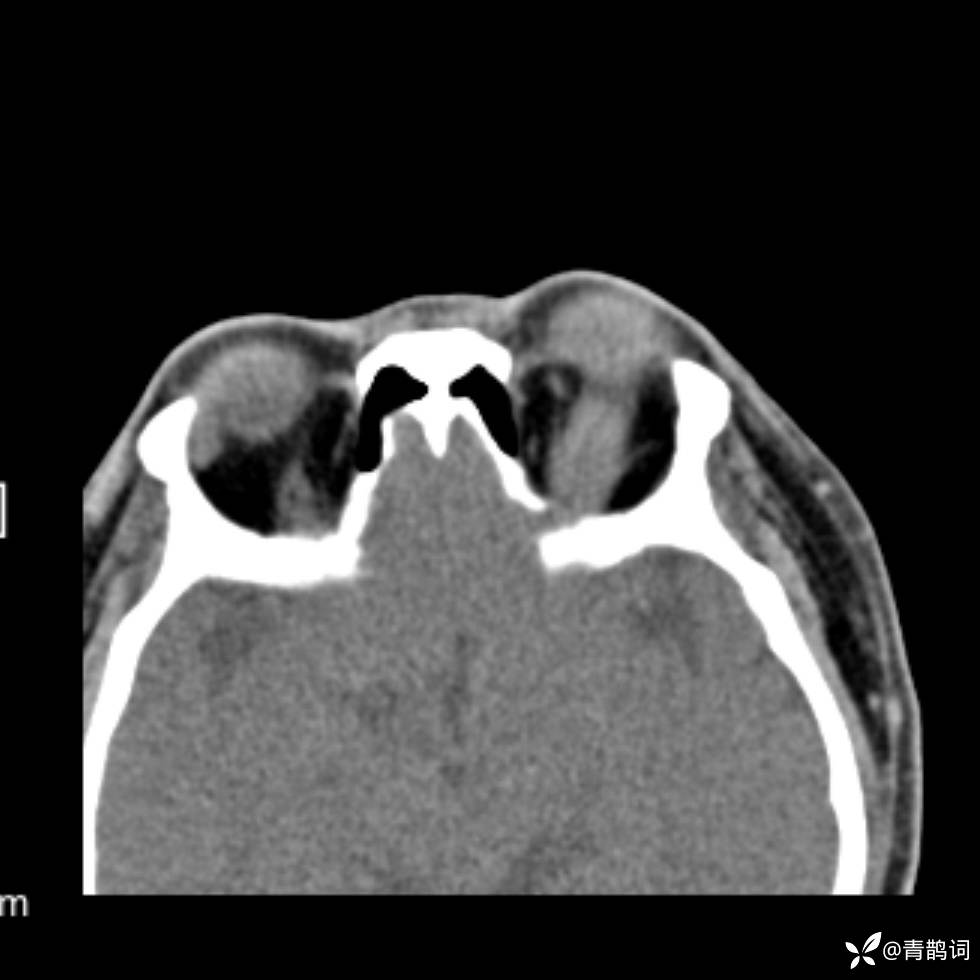

患者年龄:30岁。

患者性别:男。

简要病史:左颜面部肿胀2年,反复咳嗽咳痰,逐渐加重。

辅助检查

结合病史及影像学表现,期待评论区各位老师各抒己见~